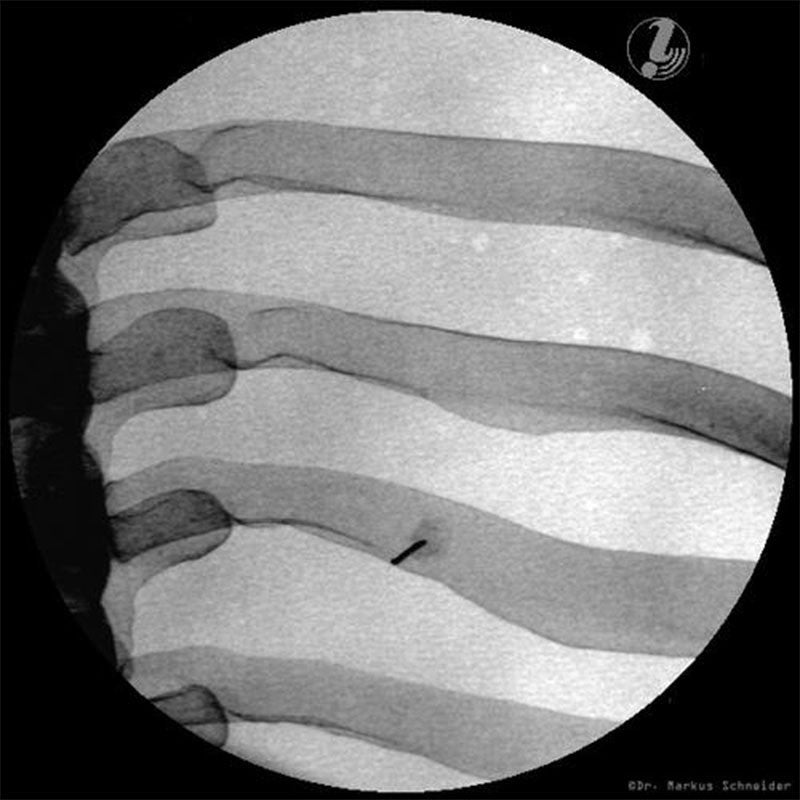

The 3B Scientific Thoracic Spine Injection Trainer allows medical professionals and students to develop a three-dimensional understanding of the practical medical procedures that take place when carrying out successful spine interventions.

Students will be taught how to correlate imaging with the thoracic spinal anatomy, which is relevant to interventional pain procedures. This knowledge will help medical students to recognise the target tissue and vulnerable structures. Using imaging and anatomic inspection, this Thoracic Spine Injection Trainer will enable students to apply best practices, ensuring patient safety whilst carrying out interventional spine procedures.

- Life-like radiopacity for realistic X-Ray images

- Anatomically accurate bone structure

- Intercostal Nerve Block (ICNB)

- Vertebrae T3-T8

- Ribs 3-8